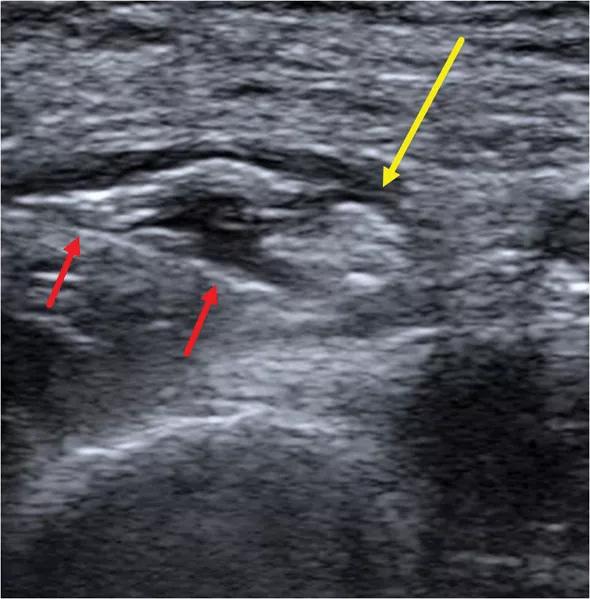

Initial imaging with MRI demonstrated no abnormal signal within the superficial branch of the radial nerve. However, subsequent ultrasound demonstrated a 3-cm segment of fascicular swelling with increased caliber of the SPN at the mid forearm between the brachioradialis, extensor carpi radialis longus, and pronator teres muscles, where the nerve exits the deep fascia (Figure 1). The radial nerve at the radial tunnel and posterior interosseous nerve were normal in appearance.

Figure 1. Transverse sonographic image demonstrating focal fascicular edema with increased caliber of the superficial branch of the radial nerve (yellow arrow).